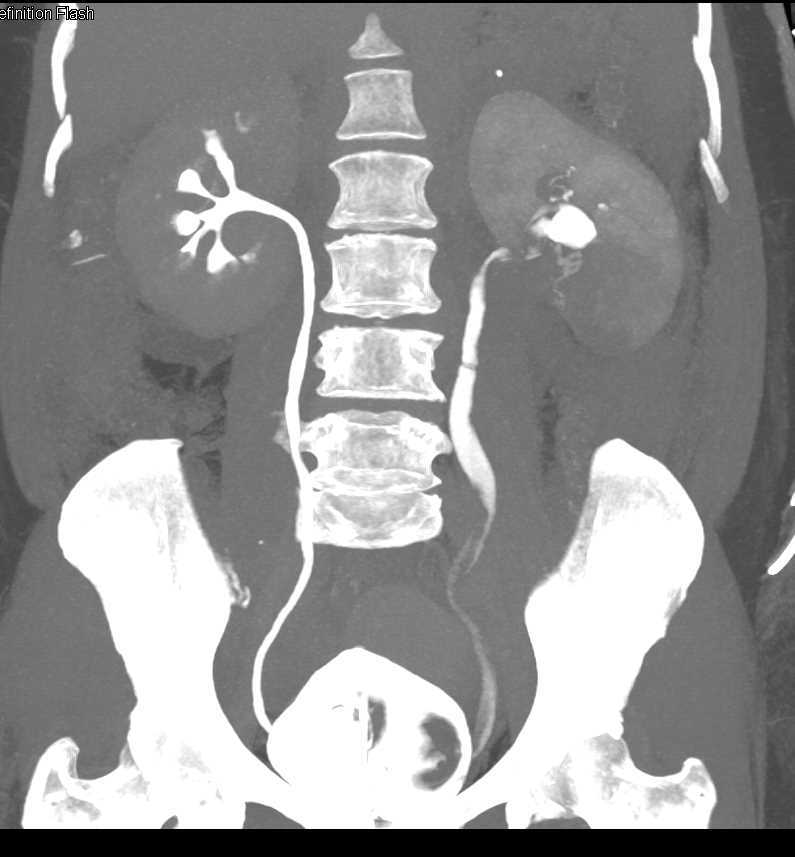

Acute Pyelonephritis Right Kidney